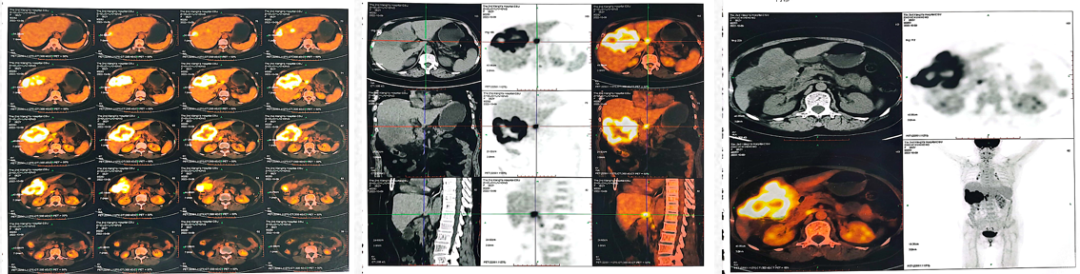

2022-10-9中南大学湘雅二院行PET/CT:肝左内叶和右前叶糖代谢增高肿块(最大横截面积10*8cm,SUVmax17.9),考虑恶性肿瘤(肝癌?胆囊癌累及肝脏?),累及胆囊及结肠肝曲及周围腹膜腔。肝门、门腔静脉间、右中腹(大网膜走行区)多发糖代谢增高的肿大淋巴结(大者约13*20mm,SUVmax 8.6),考虑淋巴结转移。盆腔子宫左后方糖代谢增高结节灶(最大横截面积15*14mm,SUVmax11.3),考虑转移所致(卵巢转移?腹膜转移)。

2022-10-9中南大学湘雅二院PET/CT